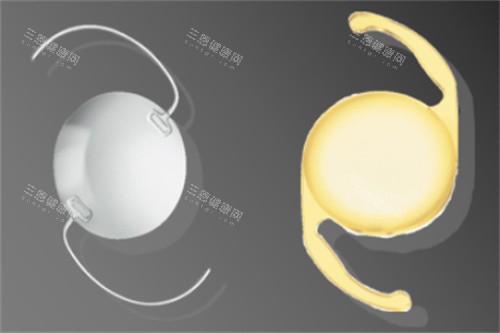

材料优势:采用Collamer专有胶原晶体,生物相容性高,紫外线过滤功能可保护眼底;

可逆性:若未来视力变化或需其他治疗,晶体可取出或更换;